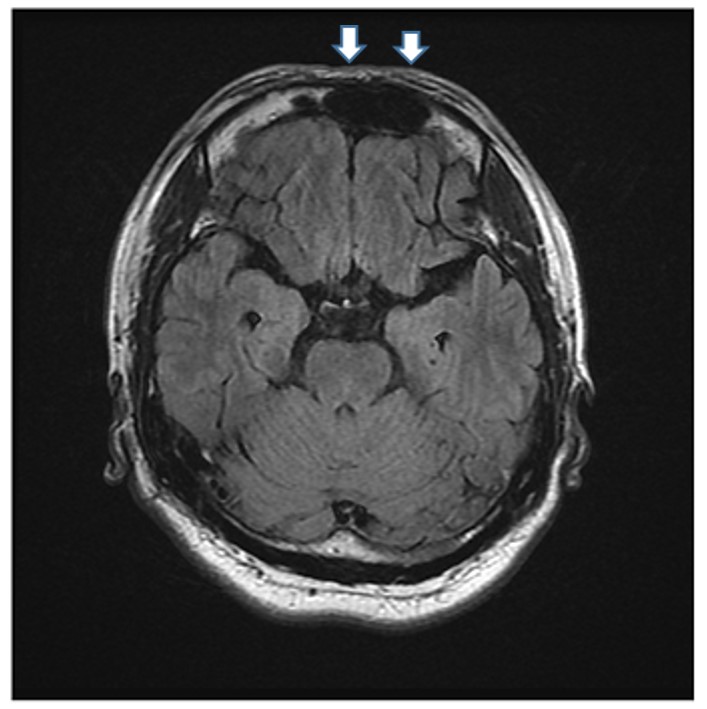

折騰一晚,隔天才接受氧氣治療,並吃了一些藥,雖症狀稍緩解,但仍是相當不舒服,一直到回到台灣,持續的頭暈頭痛才停止。但是因為仍然是間歇性頭痛,所以趕緊到永和耕莘醫院就診。想不到腦部核磁共振(MRI)檢查竟發現在顱內右前額葉有2X3公分大小的血塊(圖四、血塊如白色箭頭裡的黑色腫塊),後來繼續觀察了兩個月,在萬芳醫院追蹤的MRI檢查發現血塊終於消失了,間歇性頭痛才不再發生。

圖四:追蹤的MRI檢查發現血塊終於消失了,間歇性頭痛才不再發生。

圖四:追蹤的MRI檢查發現血塊終於消失了,間歇性頭痛才不再發生。